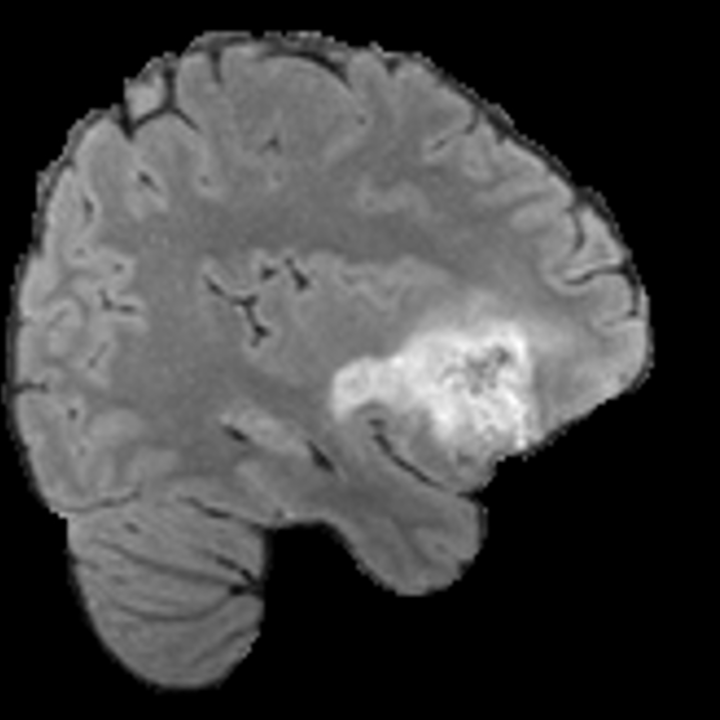

Tumour Information Preservation. For the brain tumor segmentation, we use a Swin UNETR model[28, 70], trained with random rotation, and intensity as data augmentation. On the test set with human ground-truth annotations (), the brain volumes generated from single slice input preserve the volume of the different tumour components (paired t-test, for all 3 classes). In Figure 4, we highlight the tumor profiles of the generated MRIs compared to the ground truth tumour profile. The real MRI Dice score in the test set is 85.15 while the generated MRIs from a single slice have a dice score of 83.09. This shows how the generated MRIs indeed preserve the tumor information and can act as an affordable and informative pseudo-MRI, before conducting an actual costly MRI examination in hospitals. More detailed results are provided in supplementary material.

Leveraging Context. Since we train on a predominantly cancerous brain dataset, one question that might arise is whether X-Diffusion generated MRIs preserve tumour information when the given inputs do not intersect with any tumour. We perform experiments varying the input slice index used to generate the 3D brain MRIs and measure the performance for input slices with no intersection with the tumour (not a single pixel with tumor label in the input slice). We also measure performance when only input slices are selected from tumor range. The Dice Scores of the random slices, no-tumour, and only-tumour are 83.09, 79.23, and 83.68 respectively. As can be seen here, the brain volumes generated from input slices with no tumour still preserve tumour information in reconstructed brain volumes despite a small drop in performance. This indicates that X-Diffusion is leveraging the context to preserve key information, such as tumor locations. This observation is consistent with how tumor segmentation models with global context [13] perform better than local-based U-Nets. More details are provided in supplementary material.